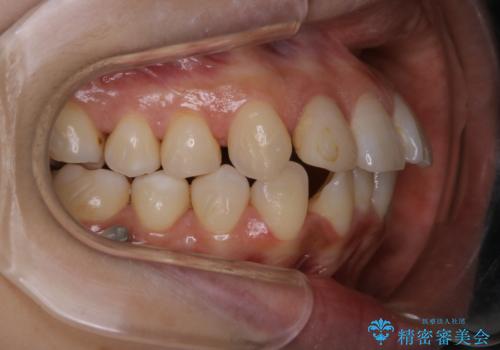

- インビザラインでのマウスピース矯正中の方です。歯についてしまったステインが気になり綺麗にしたいとのことでした。PMTC60分コースを行いました。

PMTC(保険外治療)は、毎日の歯磨きで落としきれない汚れや、コーヒ、紅茶・タバコのヤニなどの着色も除去します。目には見えない歯と歯の間・歯肉の境目・インビザライン中はアタッチメント周囲などに残っているプラーク(歯垢)もしっかり取り除きます。PMTCでは専門的な機械や材料を使用して、徹底的に汚れを除去するため、虫歯・歯周病・口臭予防などにつながります。

またPMTCを行うことで、ご自身本来の歯の色になり自然な明るさになります。